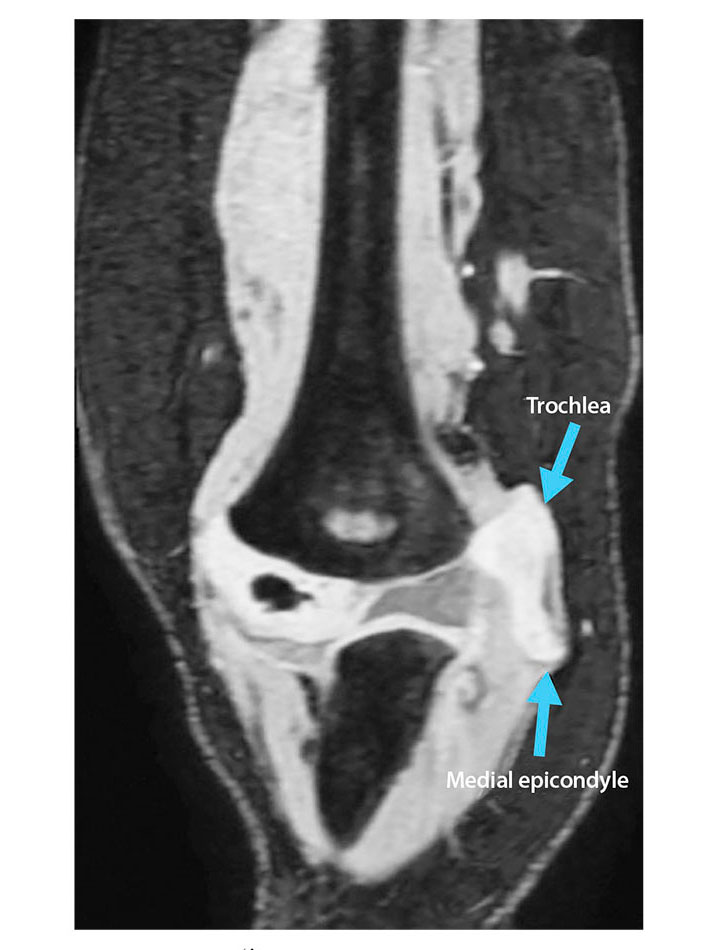

MR images revealed an avulsion fracture of the right medial condyle and epicondyle. The fragment was displaced medially and rotated; the articular surface was oriented laterally facing the distal humerus, which correlated with the calcification seen on previous radiographs. The displaced, predominately cartilaginous, trochlear and medial epicondyle fracture fragment was visible on cartilage-specific fat-suppressed T1 volume sequences (see Figure 3). MR images were sent to the 3-D Innovation Laboratory and processed into 3-D volume-rendered images for surgical planning using a sequence that isolates bone and cartilage from adjacent structures. Orthopedic surgeons evaluated the images, and determined that an open reduction and internal fixation surgical procedure was required. They performed the procedure on the trochlea and medial epicondyle, using Kirschner wires to repair the fracture. A postoperative radiograph, obtained while the elbow was in a cast, showed Kirschner wire placement and confirmed fracture repair (see Figure 4).

Figure 3. Magnetic resonance image showing a medially displaced and rotated avulsion fracture of the trochlea and medial epicondyle. Image courtesy of the authors.